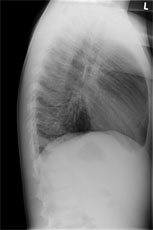

Radiologie Quiz 45

Zur Aufnahme kommt ein 8 jähriger Knabe mit hartnäckigem, vorwiegend trockenem Reizhusten seit 5 Tagen und subfebrilen Temperaturen bis mässigem Fieber.

Bei relativ blander Klinik wird ein Thoraxröntgen durchgeführt:

Thorax seitlich

Welcher Befund liegt vor? (mehrere richtige Antworten möglich)

Wie lautet Ihre Verdachtsdiagnose? (mehrere richtige Antworten möglich)